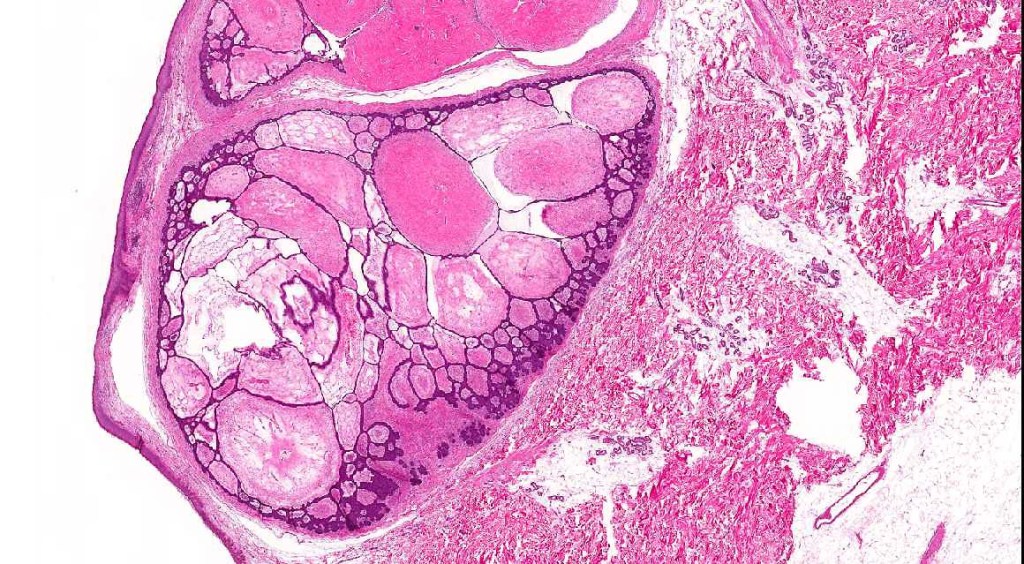

Histological features

•Multifocal origin from epidermis

•Anastomosing basaloid, narrow epithelial strands associated with a prominent fibrous (sometimes myxoid) stroma

•Peripheral palisade

•Retraction artifact variably present

•Occasional cysts